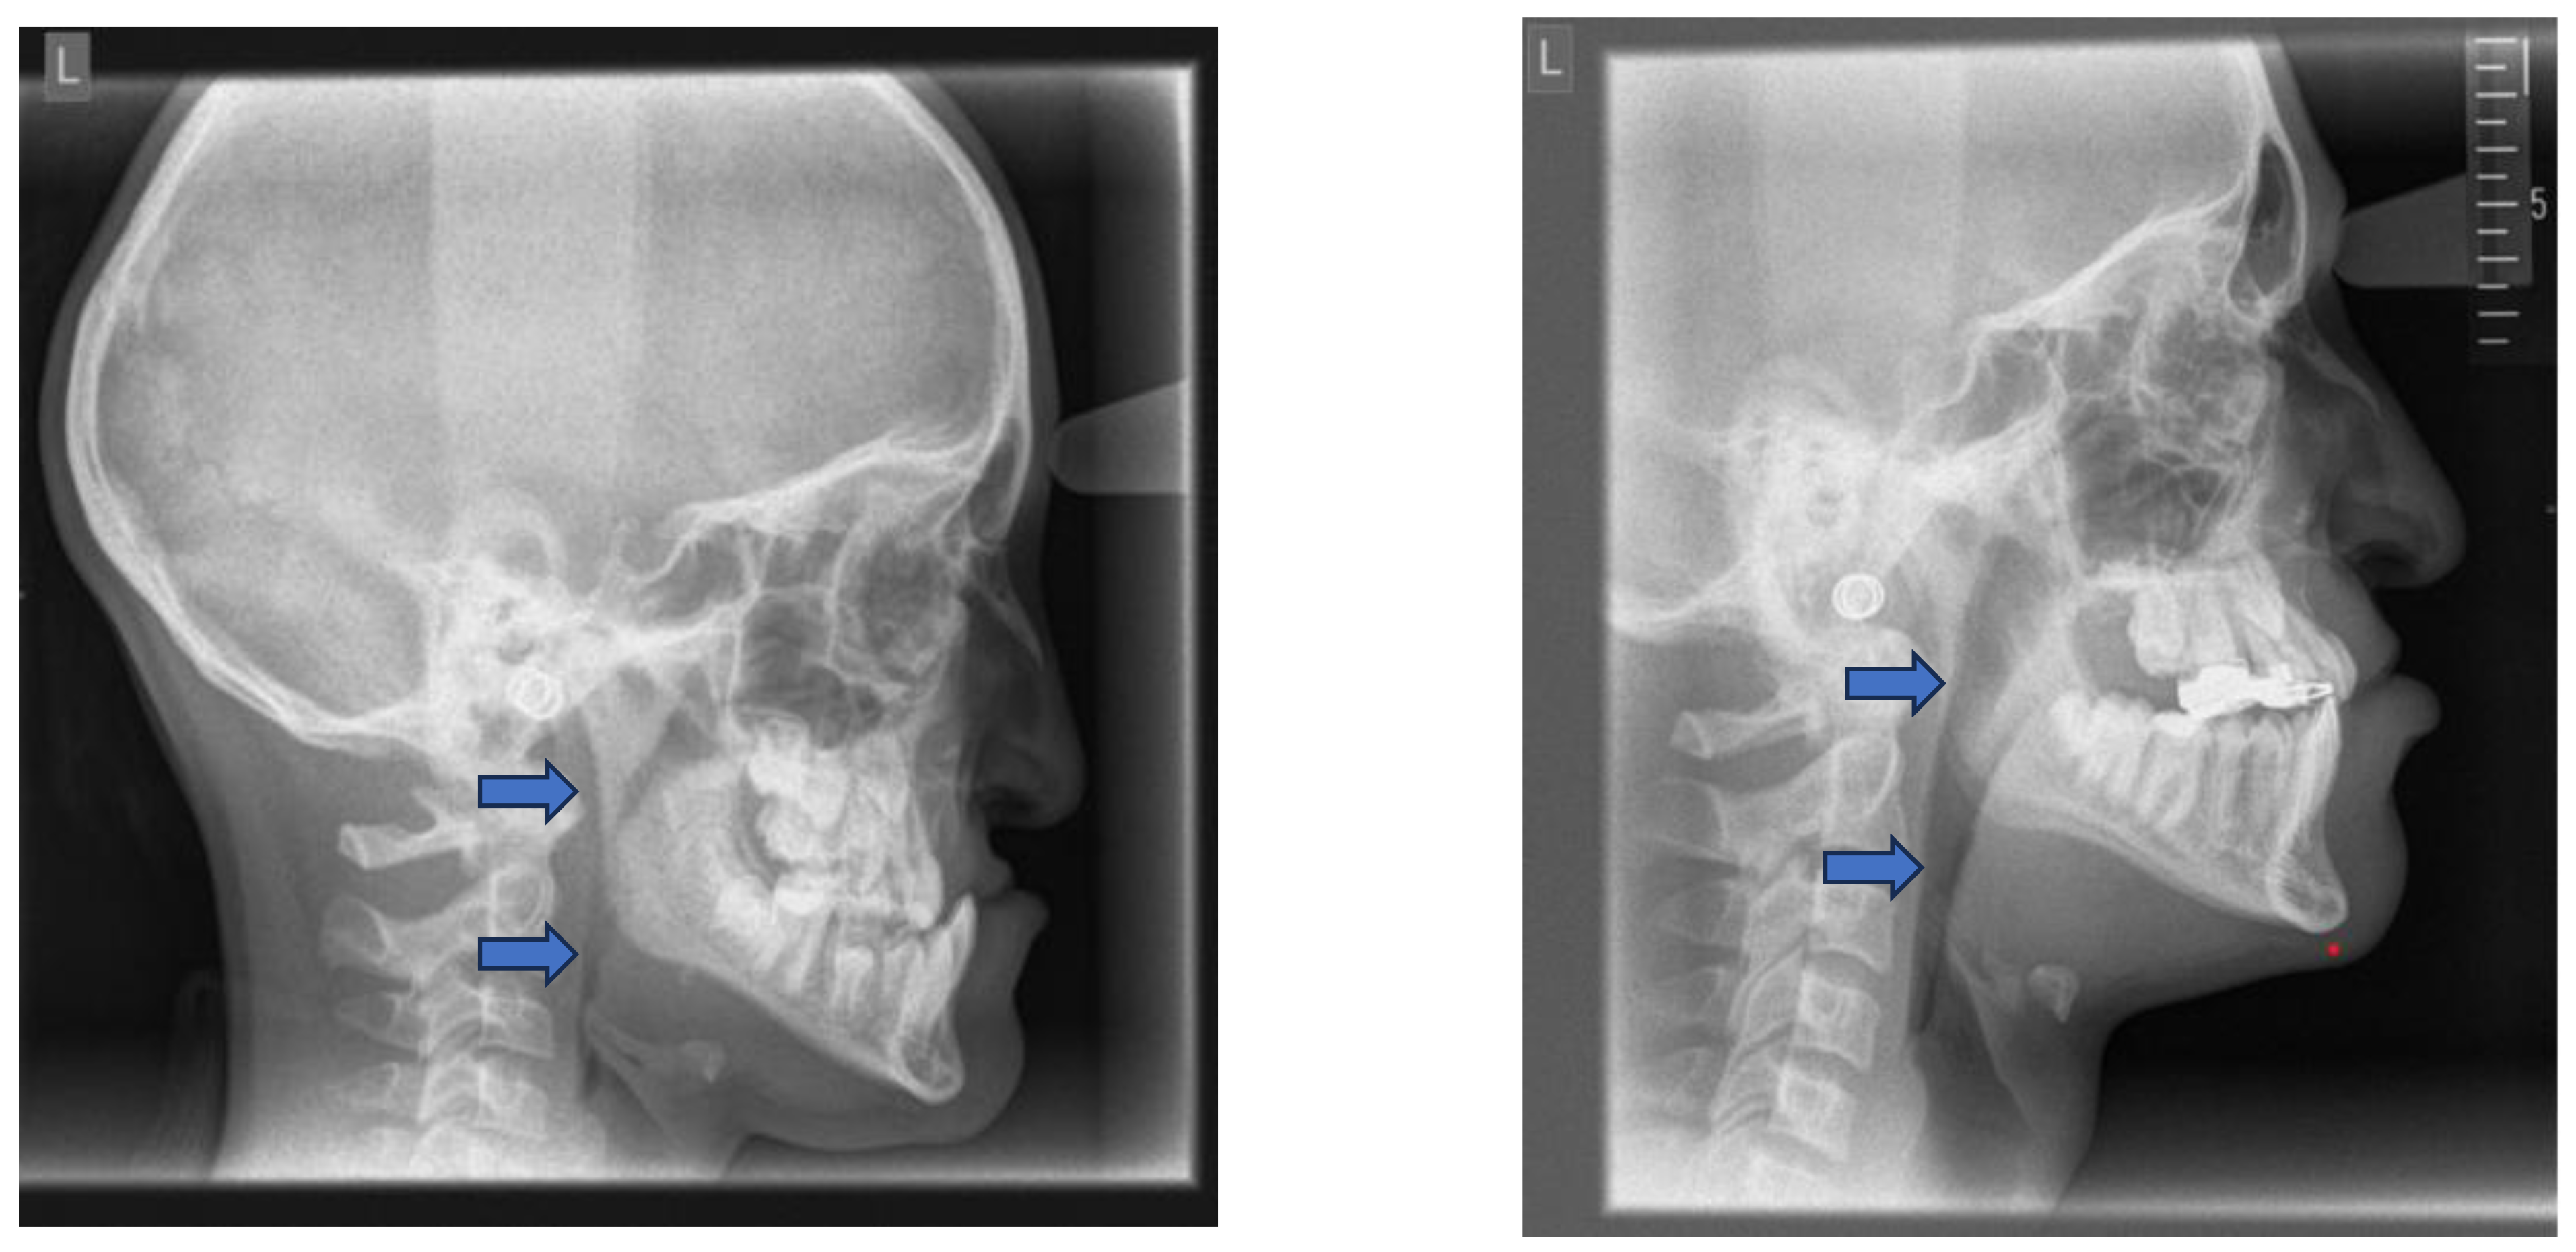

7. Imaging and Radiologic Assessment

Lateral cephalometry has several advantages in assessing craniofacial morphology, including both hard and soft tissues, and identifying the sagittal dimension of the posterior airway space [84,85]. This diagnostic tool is reproducible, affordable, easily accessible in an orthodontic office, involves minimal radiation exposure, and is non-invasive [2]. (Figure 6) The cephalometric radiographs are taken in an upright and natural head position, where eyes focus ahead with a horizontal visual axis parallel to the floor (Frankfort horizontal plane). The occlusion should be the habitual bite (not forced into maximum intercuspation) and the lips in gentle contact (not forcefully closed). Lateral cephalometry can be used as a screening tool for assessing craniofacial morphology of hard and soft tissues and airway and identifying the sagittal dimension of the smallest airway dimension [84,101].

Nevertheless, it is essential to note that soft tissues in the upper airway behave differently when a person is asleep, in a supine position, compared to an upright position [86-89]. Several studies attempted to establish a relation between oropharyngeal dimensions and craniofacial structures in subjects with sleep disorders and with OSA through cephalometric assessment [90-92].